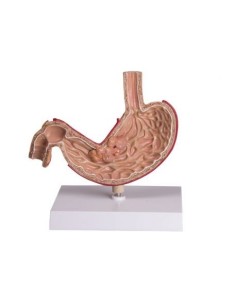

Scopri il Mondo dell’Anatomia con Modelli anatomici di Precisione

Modelli Anatomici Dettagliati per Ogni Necessità

Dal cranio in 22 parti con incastri magnetici ai modelli di colonna vertebrale, da quelli di articolazioni a quelli di cuore, ogni pezzo della nostra collezione è progettato per un’immersione totale nello studio dell’anatomia umana. I nostri modelli, realizzati tramite scansioni di ossa vere, garantiscono un’esperienza tattile autentica e una fedeltà di peso quasi identica agli originali.

Strumenti Didattici Innovativi per l’Educazione e la Pratica Medica

Essenziali per studenti e professionisti, i nostri modelli anatomici sono strumenti didattici che permettono di osservare le strutture anatomiche con precisione, eliminando la necessità di dissezioni o studi invasivi. Sono inoltre utili per spiegare ai pazienti le patologie, rendendo la comunicazione più efficace e risparmiando tempo prezioso.